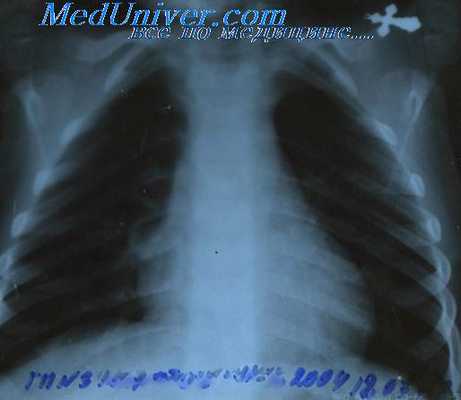

Рентгенография грудной клетки. Рентгенография грудной клетки является очень важной процедурой обследования. Часто наблюдается увеличение размеров средостенных и бронхолегочных лимфатических узлов. На рисунке выше показано анатомическое расположение основных групп лимфатических узлов. Аденопатия средостенных узлов особенно характерна для женщин с нодулярным склерозом. Может наблюдаться очень сильное увеличение размеров средостенных узлов, приводящее к обструкции верхней полой вены.

В патологический процесс может быть вовлечена зобная железа. При этом на снимке в правой боковой проекции видно плотное образование и на боковом снимке оно видно спереди. Увеличение размеров бронхолегочных лимфатических узлов может сопровождаться незначительными изменениями на рентгеновском снимке. Обычно увеличение размеров бронхолегочных узлов отмечается наряду с увеличением лимфатических узлов средостения.

Изменения в легких могут быть вызваны обтурацией бронхов, из-за увеличения размеров внутриорганного лимфатического узла или, реже, из-за локализованной внутрилегочной формы болезни Ходжкина. Обтурация бронха может вызвать ателектаз доли легкого со склеротическими изменениями в спавшей области. Нередко пораженные лимфатические узлы непосредственно затрагивают легкое. При рентгенографическом обследовании больных, прошедших курс облучения средостенных лимфатических узлов, поражение легкого иногда сложно отличить от радиационной пневмонии и фиброза.

Похожую рентгенограмму дают туберкулез и другие инфекционные заболевания. На снимке также может наблюдаться расширение тени сердца, вызванное выпотом в полость перикарда, либо эрозией ребра или грудины, вследствие локального распространения опухолевого процесса от лимфатических узлов.